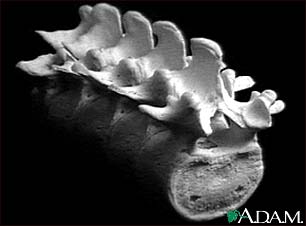

급성요추염좌 척추는 우리몸을 지탱하며 척추신경을 주관하는 중요한 역할을 하는 것으로 목(경추)7개, 등(흉추)12개, 허리(요추)5개, 천추와 꼬리뼈(미추)등약 32~34개의 추골로 이루어져 있다.

미국 캘리포니아 샌프란시스코 대학병원 정형외과 의사인 Livermore 교수의 발표에 따르면 급성 요추염좌는 요통환자의 약 5%정도를 차지한다고 하는데, 요추 염좌는 발목이 삐긋 했듯이 허리가 삐었다는 말이며, 척추에 있는 관절은 척추체 사이에 관절인 추간판 즉 흔히 말하는 디스크와 함께 후방 척추관절로 양쪽에 있는 추간관절(facet joint)이 척추를 뒤쪽에서 고리처럼 연결되어있다. 요추 염좌는 흔히 일어나는 일이지만 단순히 근육이 손상된 경우부터 인대가 손상된 경우 (흔히 이럴 때 인대가 늘어났다고 한다), 추간판에서 수핵을 둘러싸는 막인 섬유륜의 일부 가 찢어지는 경우 등 여러 가지 상태가 있는데, 근육만 다친 경우라면 며칠 안 가서 치료 가 되지만 추간판에서 수핵을 둘러싸는 섬유륜의 일부가 찢어진 경우라면 추간판 탈출증(허리 디스크병)의 원인이 된다. 또한 외력에 의해 척추 후방부의 추간관절과 관절주위의 인대가 손상이 생겨 심한 요통이 발생하며, 이 추간관절은 매우 제한된 범위의 관절운동만을 할 수 있어 생리학적으로 인대와 관절면이 견딜수 없는 외력이 허리에 가해지면 인대와 관절면이 손상받고, 작은 허리 움직임만으로도 손상된 관절면을 건드리게 되어 심한 통증과 허리의 운동장애가 발생하게 되는 것이다. 대부분 준비되지 않은 상태에서 무거운 물건을 허리의 힘으로만 들어올리려 했을때, 원하는 동작과 반대되는 역동작을 갑자기 하려고 할 때, 부지불식간에 큰 외력에 의해 허리가 갑자기 굽혀지는 동작이 발생될 때 (안전 밸트 착용시 차의 급정거), 앉은 자세에서 바닥의 물건을 주우려고 몸을 뒤틀어 숙였을 때가 가장 흔한 원인이 된다. 악 소리도 못하고 입이 딱 벌어질 정도로 요통이 발생하며 그 자리에서 꼼짝도 못할 정도로 매우 심한 경우가 많고, 허리를 조금만 움직이려해도 몹시 괴로운 요통이 발생하며 가만히 있더라도 허리 근육이 뻣뻣하게 굳어 가는 느낌이 든다.